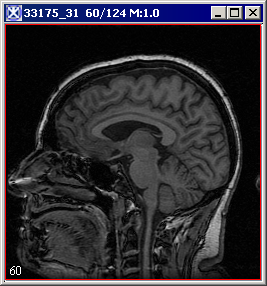

[2dHistogram.html#wp1556615 Figure 10] shows the two input images, the output 2D histogram image and its lookup table.

Figure 1. Two input images, output 2D histogram image and its lookup table